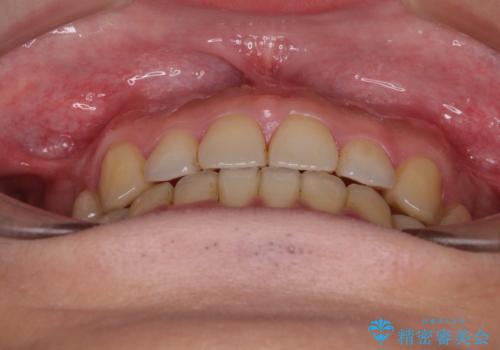

- 抜歯矯正の後戻りを気にして来院された患者様です。

舌の突出癖によるオープンバイトになり、前歯の叢生が後戻りしていました。

舌のトレーニングを行いながら、インビザラインを用いて矯正治療を行うこととしました。

インビザラインの特性を活用して奥歯の咬み合わせを圧下させることで、前歯のオープンバイトを改善さえることができました。